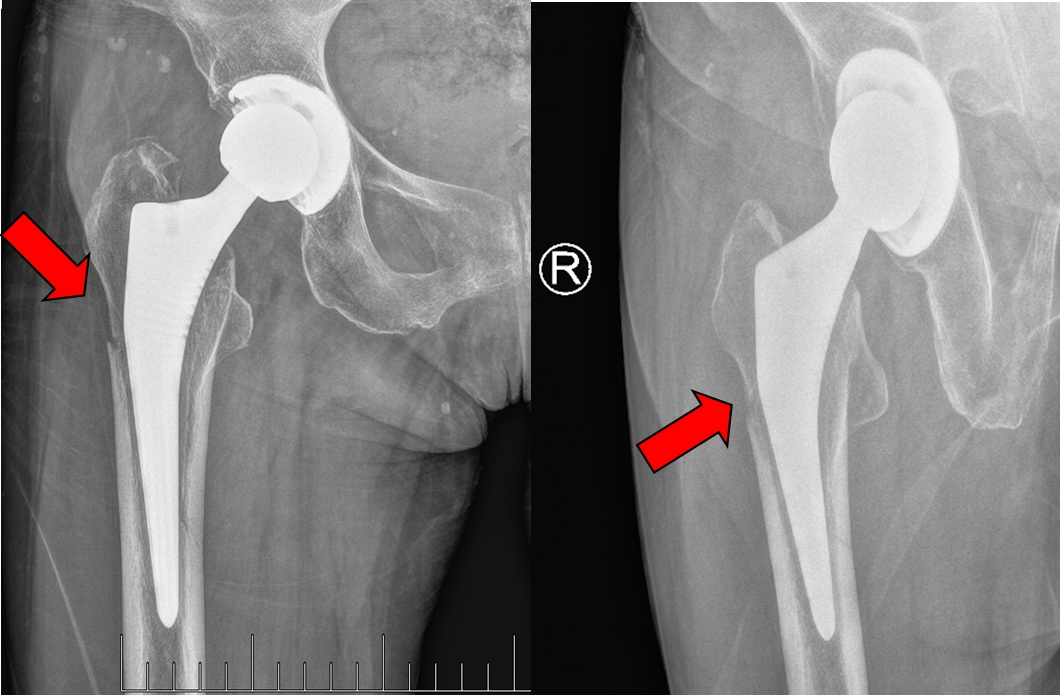

王女士二次受伤后影像检查提示假体周围骨折

然而在2025年春节期间,王女士在商场搭乘手扶电梯时不慎摔倒,出现右髋疼痛,肢体活动受限,家属陪同王女士再次来到苏大附四院就诊,检查结果显示王女士此次外伤导致了右侧髋关节假体周围骨折,且假体已经松动。此类关节置换术后的假体周围骨折伴松动是骨科公认的棘手难题,要解决这个难题的最佳办法是施行翻修手术。与初次手术不同,翻修手术难度与术后并发症的发生率都要高得多。姜为民主任和林俊主任对患者王女士此次髋关节翻修手术十分重视,与杨小海主任一同进行了术前的讨论,制定了详细的手术方案。手术当天,在麻醉手术科的积极配合下,杨小海主任团队顺利完成了本例髋关节翻修术。